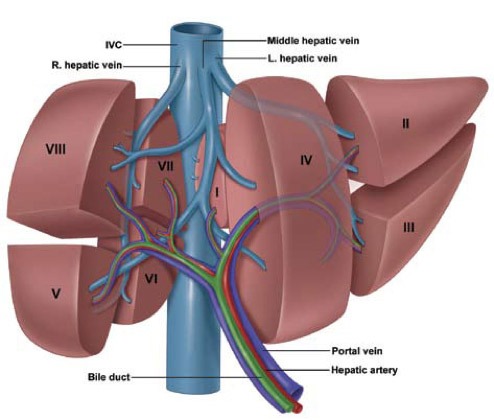

Cirurgia: A cirurgia é uma das principais opções de tratamento para o câncer de fígado, especialmente quando o tumor é ressecável.

Ressecção Hepática: Remoção da parte do fígado onde o tumor está localizado. Pode ser uma opção curativa para tumores pequenos e em estágio inicial.

Transplante de Fígado: Substituição do fígado doente por um fígado saudável de um doador. Indicado para pacientes com doença hepática em estágio inicial e cirrose avançada.

Ressecção Hepática Metastática: A remoção cirúrgica das áreas do fígado afetadas por metástases colorretais. Pode ser realizada em pacientes com um número limitado de metástases e função hepática adequada.

A Importância do Tratamento Cirúrgico

A cirurgia oferece a melhor chance de cura para pacientes com câncer de fígado em estágio inicial e para aqueles com metástases hepáticas de câncer colorretal ressecáveis. A remoção completa do tumor ou das metástases pode levar à remissão da doença e melhorar significativamente a qualidade de vida do paciente. Mesmo em casos avançados, a cirurgia pode ajudar a controlar os sintomas e prolongar a sobrevivência.